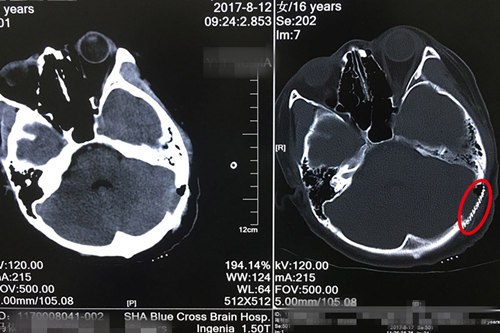

术后CT显示:钛网与颅骨结合紧密,未见明显异常病灶。

话虽然这么说,可是静静小脑内的这个病灶已长成一颗花生那么大,将枕骨穿透了一个手指粗的洞。而且这个病灶与粗大的静脉窦(静脉汇合形成的血管腔,构成特殊的颅内静脉管道,输送颅内静脉血)紧密粘连,最狭窄的地方还不到1毫米的距离。既要把病灶切除干净(防止复发),又不能损伤血管(如果血管破裂,后果不堪设想),手术室的助手医生和护士都替侯主任捏一把汗。最后,凭借着多年积累下来的娴熟技艺和沉稳作风,侯主任完美切除了病灶,保留了血管,保护了脑组织,手术顺利结束。